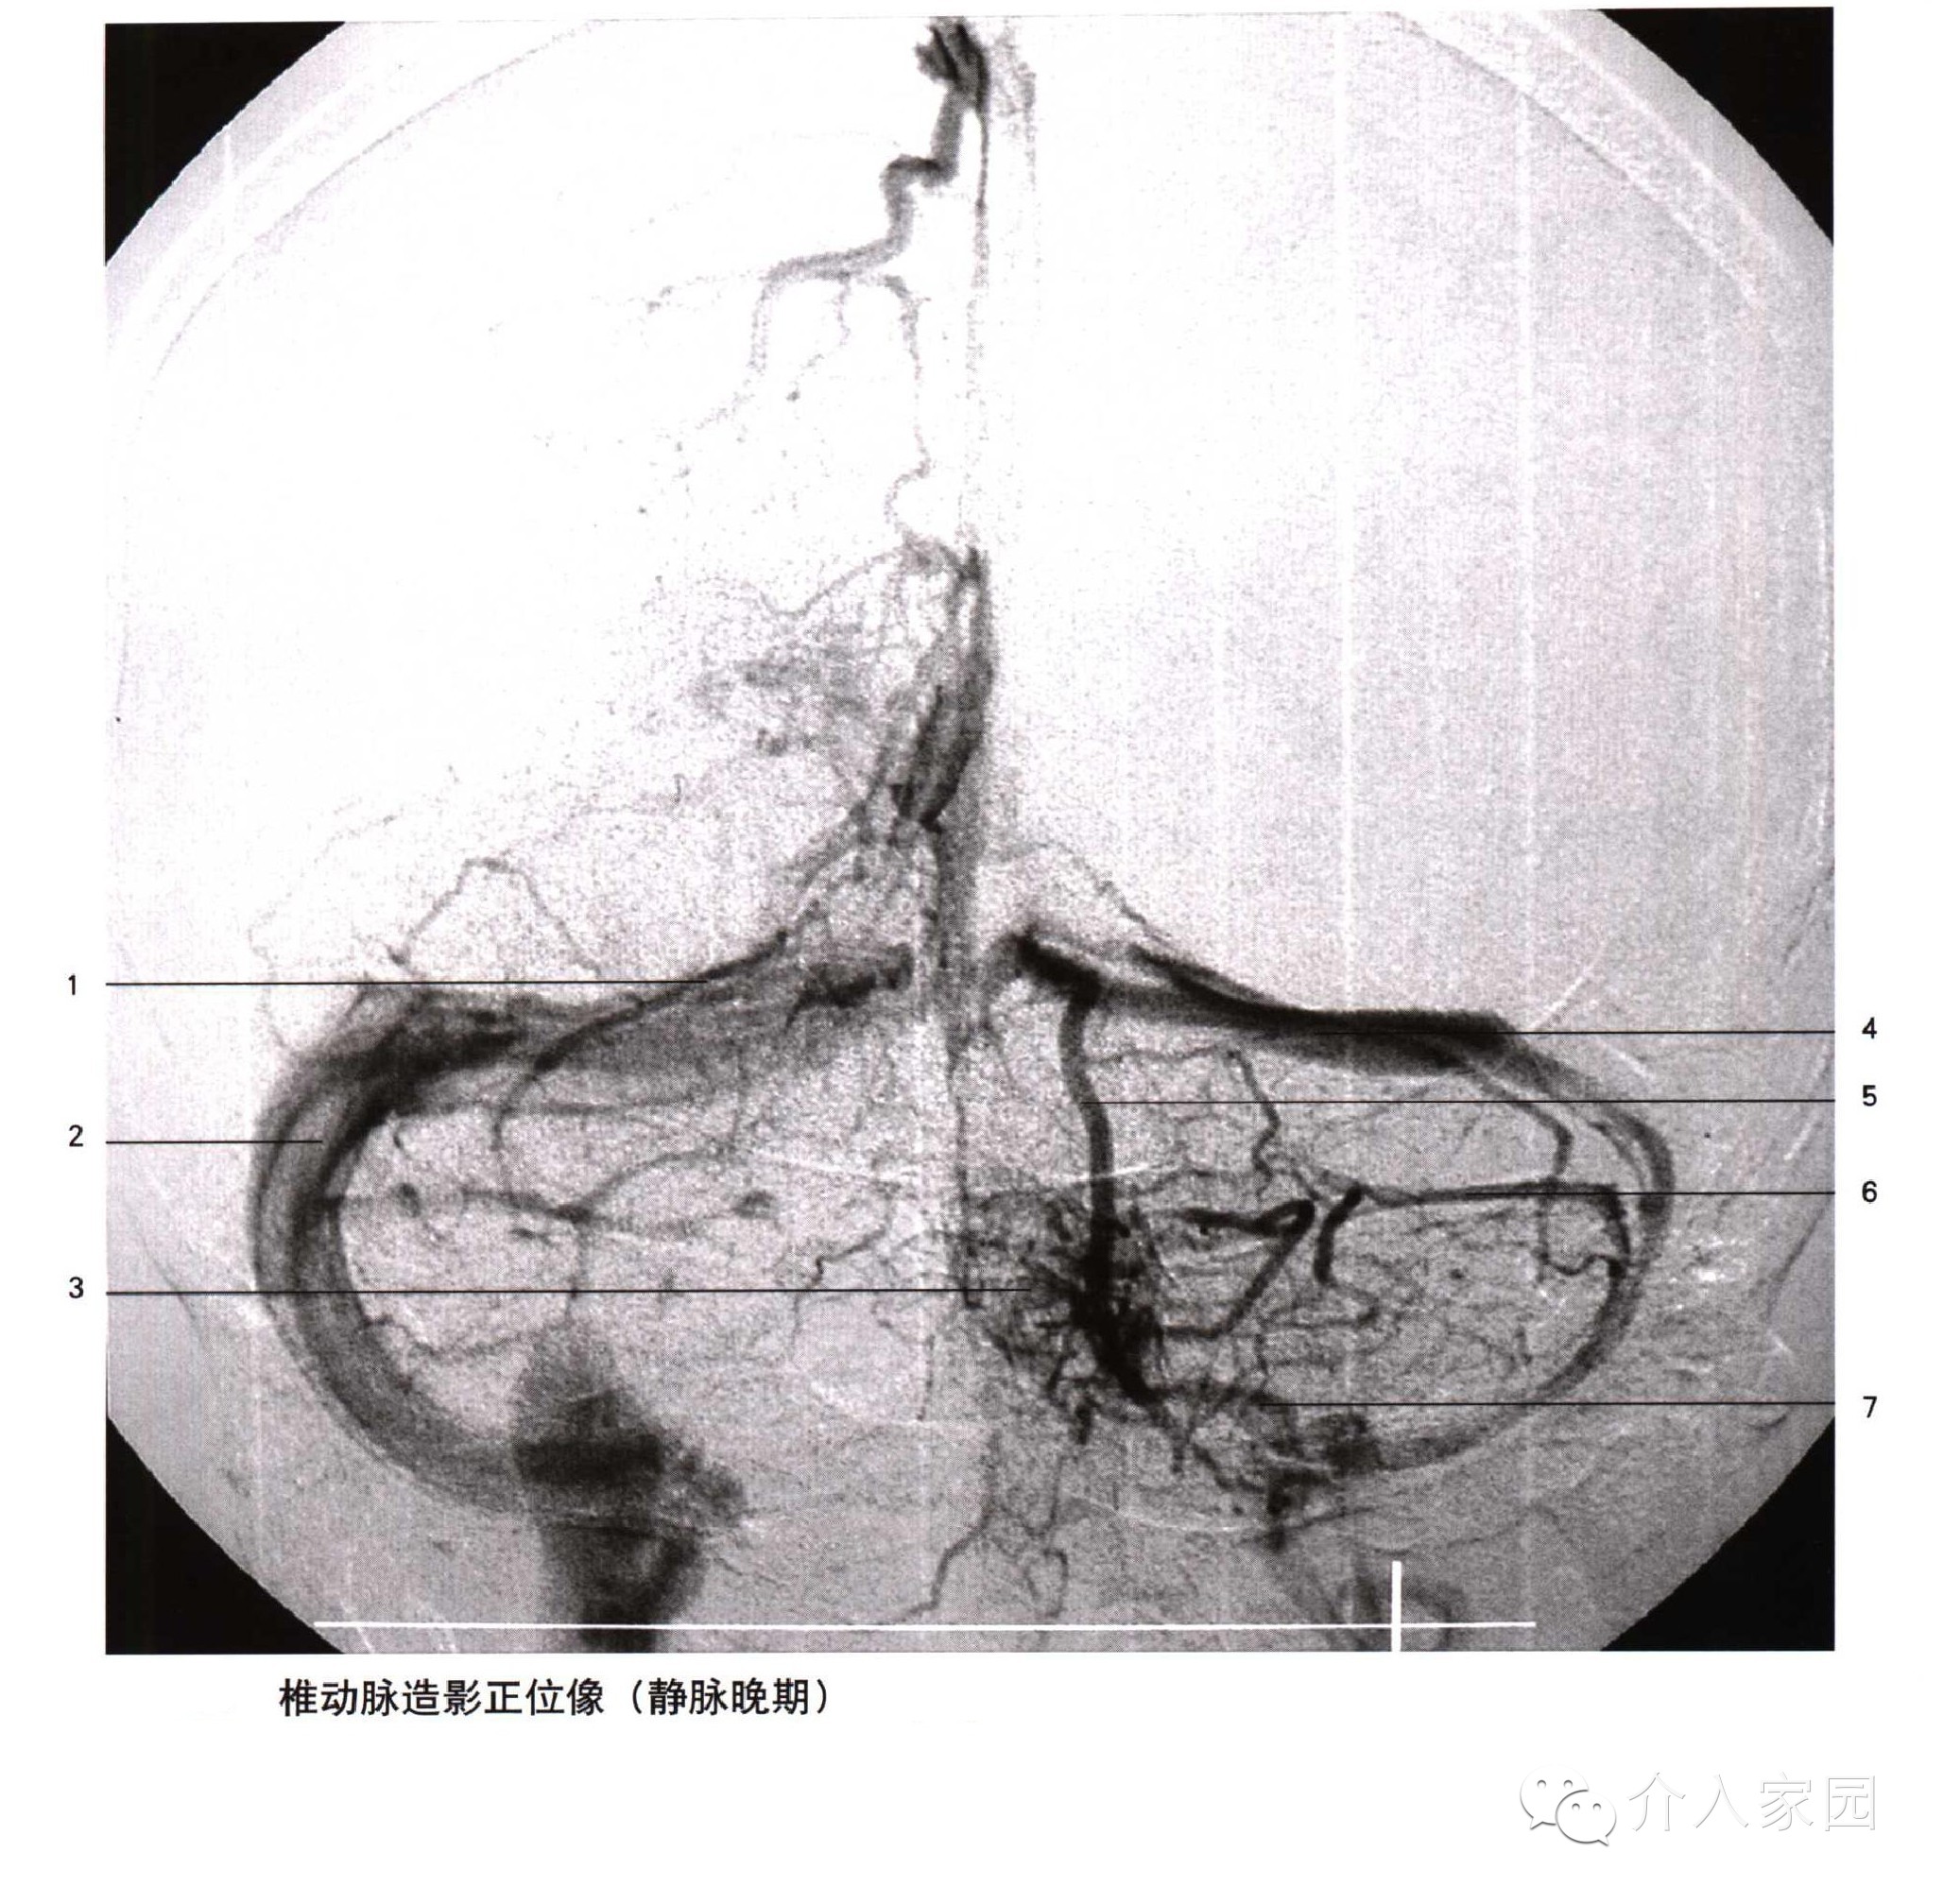

1、上矢狀竇 2、頂升靜脈 3、枕升靜脈 4、直竇 5、竇彙 6、橫竇 7、乙狀竇 8、中央溝靜脈 9、上吻合靜脈 10、額升靜脈

11、丘紋靜脈 12、靜脈角 13、大腦內靜脈 14、透明隔靜脈 15、基底靜脈 16、大腦中淺靜脈 17、海綿竇 18、岩下竇